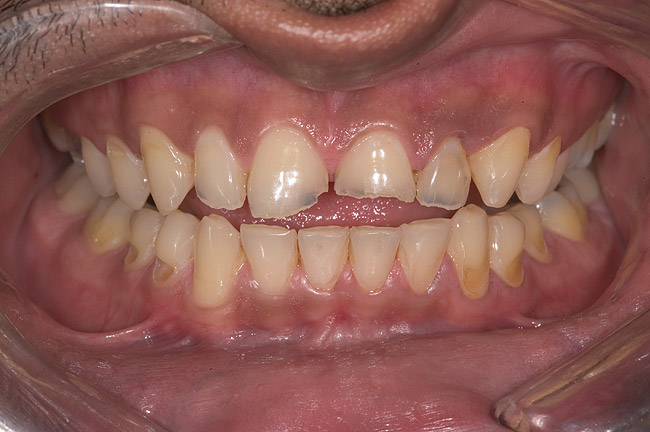

Figure 5  Thinning of the labial enamel and noncarious cervical lesions.

Figure 5

Examination revealed that palatal surfaces of teeth Nos. 6 through 11 showed severe loss of tooth structure, with mild wear on the lower incisors and loss of anterior guidance (Figure 5 through Figure 7). The palatal TSL was consistent with the clinical picture presented by patients with gastric reflux. A detailed medical history was taken, and the patient complained of having heartburn and acidity at least 4 out of 7 days a week. He had never sought treatment for it and used over-the-counter medication when needed. He was a nonsmoker, with occasional intake of alcohol. He had a high-stress job with irregular meal times. A thorough smile and dental analysis11 was carried out; the findings appear in Table 2.